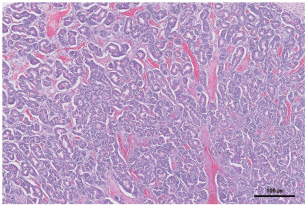

Histopathological examination of the pancreas revealed moderately well-differentiated pancreatic acinar cell carcinoma. Neoplastic cells were arranged in numerous variably sized interconnecting acini surrounded by and supported by a fine fibrovascular stroma. The acini contained intraluminal, pale, eosinophilic, and homogenous material (Fig. 6).

Fig. 6. Histopathological examination of the pancreas revealed a large pancreatic acinar cell carcinoma that was moderately well-differentiated. The neoplastic cells were arranged in numerous variably sized, interconnecting acini surrounded by and supported by fine fibrovascular stroma. The acini contained intraluminal, pale, eosinophilic, homogenous material (H&E stain, × 200 magnification, bar=100 μm).